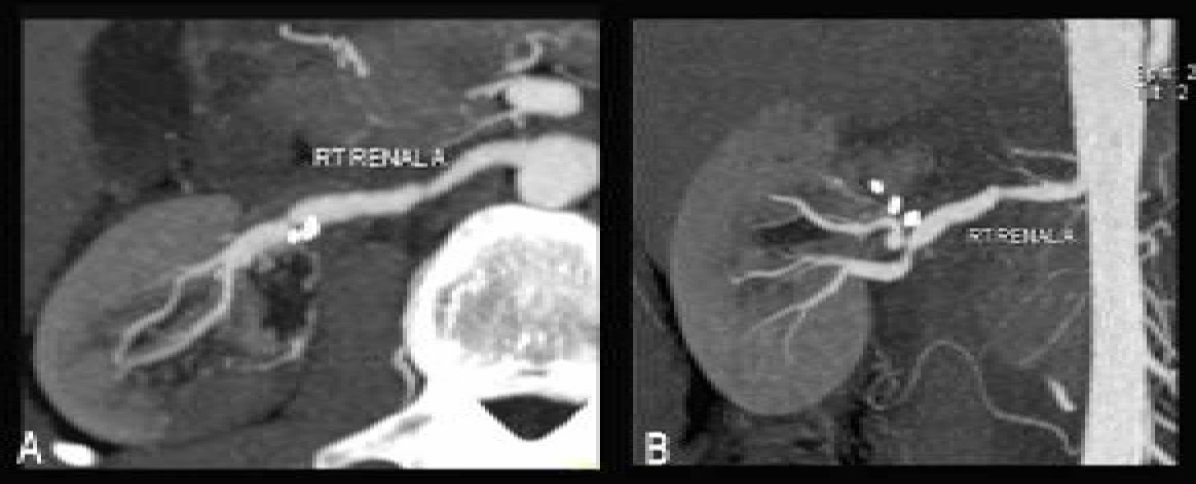

Renal artery duplex scan and contrast CT scan abdomen showed multiple aneurysms in distal right renal artery and stenoses proximal and distal to them (figure 1A, B). Tc DTPA Captopril renogram was done to assess renal function, which showed smaller right kidney with prolonged T max, which accounted for 39.1% of total renal function (figure 2A, B).

Figure 1: Preoperative CT Angiogram images: A) Coronal reconstruction and, B) Axial view showing 'Bunch of Grapes' sign of right renal artery.